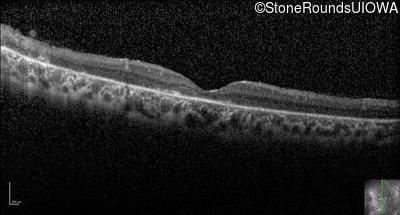

Optical Coherence Tomography - Left - 20/32 +1

Exemplar / OCT Stack

OCT Stack